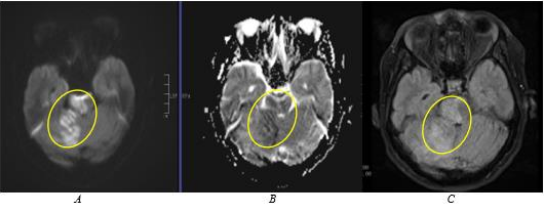

The last case is of a 60-year-old female, right-handed, with no known co-morbidities, and a pre-morbid mRS of 0, presenting at the emergency department of another institution with acute, persistent rotatory dizziness and gait imbalance. Initial NIHSS was 11 for drowsiness, dysconjugate gaze, and ataxia. A plain cranial CT scan was facilitated revealing no acute infarctions or haemorrhage; hence administration of intravenous thrombolysis was done decreasing the NIHSS to 9. The patient was transferred to our institution for closer monitoring. Upon arrival at our institution, she developed new onset left homonymous hemianopsia. The repeat cranial MRI and MRA (Figure 3.) revealed several tiny acute infarctions in the right cuneus, precuneus, lateral occipital, and lingual gyri.

Figure 3. Areas of restricted diffusion with corresponding signal drop-out along the right hemipons, and right cerebellar hemisphere